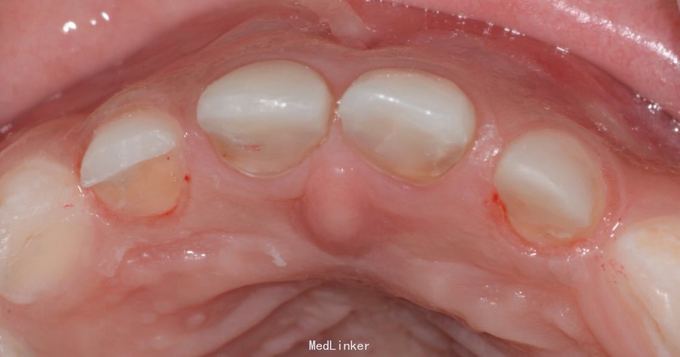

儿童6岁乳上前牙只剩牙根,唇侧牙龈有瘘管口半月,特来就诊

A1 B1 残根,可探及根管内,有黑褐色腐质物,扣(-),探(-),无松动,唇侧牙龈微红肿,各有一个瘘管口,压有浓液渗出物,A2 B2残根,呈黄褐色扣(-),探(-),无松动。

A1 B1残根,根尖炎。 常规根管治疗,树脂充填,抛光 A2 B2残根,常规去腐,备洞,树脂充填,抛光